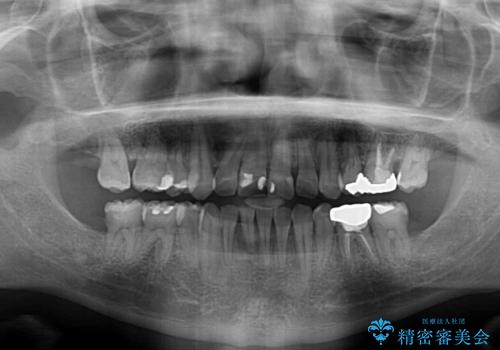

口元の突出感はないものの、上顎前歯のデコボコが著しかったため、上下顎左右小臼歯4本を抜歯することとしました。

上下の正中位置を改善するため、右下は第一小臼歯を、その他は第二小臼歯を抜歯することとしました。

第二小臼歯抜歯の矯正治療は、治療期間が長引くことが多いですが、動きが非常に良く、予定の治療期間で終えることができました。

上下の正中も思っていた以上に良い位置に改善されました。